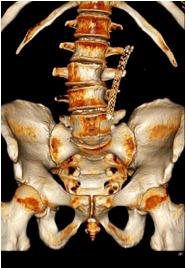

Funding: None

Authors’ contributions: M A A D , W D C M , A M T

Acknowledgments: None

REFERENCES